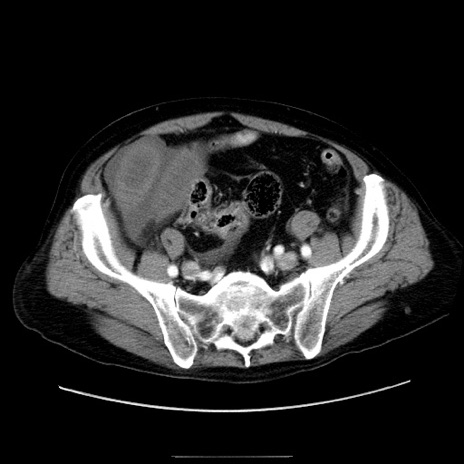

症例30(横断像)

【症例】80歳代男性

【主訴】臍周囲痛

【現病歴】約6時間前から臍下部痛が出現。次第に腹部膨隆・背部痛も生じてきたため来院。背部痛の場所は変化しない。

【身体所見】意識清明、BT 36.3℃、BP  131/87mmHg、P 87bpm、SpO2 100%(RA)、臍周囲自発痛・圧痛あり、反跳痛なし、自発痛部位に一致して板状硬あり、腹部膨隆、腸雑音減弱、CVA tenderness両側陰性。

【データ】WBC 19600、CRP 0.33